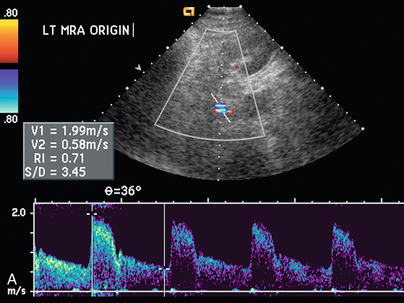

Для прямой спектральной допплеровской диагностики РАС были предложены различные критерии, что вызвало разногласия. PSV более 200 см/с ( рис. 9-12 ) был предложен для допплеровской диагностики уменьшения диаметра почечной артерии на 60%. В недавнем метаанализе PSV был лучшим критическим фактором в диагностике РАС с чувствительностью и специфичностью 85% и 92% соответственно. 29 Соотношение PSV почечной артерии и PSV аорты (RA/Ao) является еще одним критерием, предлагаемым для диагностики РАС. Соотношение RA/Ao PSV более 3,5:1 ( рис. 9-13 ) предполагает значительный уровень РАС, обеспечивая чувствительность 91% и специфичность 91%. Повышенное соотношение пиковой систолической скорости почечной артерии к систолической скорости дистальных почечных артерий также было предложено в качестве критерия диагностики РАС. Одно исследование 187 почечных артерий с ангиографической корреляцией также показало, что абсолютная почечная междолевая скорость PSV менее 15 см/с приводила к чувствительности и специфичности 87% и 91% соответственно для допплеровской диагностики 50% стеноза.Цзянь-Чу и др. недавно изучили влияние атеросклероза и возраста на параметры допплерографии для диагностики РАС и предполагают, что использование диагностических порогов почечно-аортального соотношения и почечно-междолевого соотношения различается у пациентов старше и моложе 46 лет. На другие сонографические критерии в их исследовании возраст пациентов существенно не влиял.

РИСУНОК 9-13. Стеноз почечной артерии. (А) Дуплексная допплерография почечной артерии демонстрирует пограничную пиковую систолическую скорость, 199 см/с. (B) Спектральная допплеровская волна аорты показывает, что максимальная скорость составляет 59 см/с. Рассчитанное отношение пиковой систолической скорости почечной артерии к аорте, равное 3,72, превышает порог 3,5, что указывает на значительный стеноз.